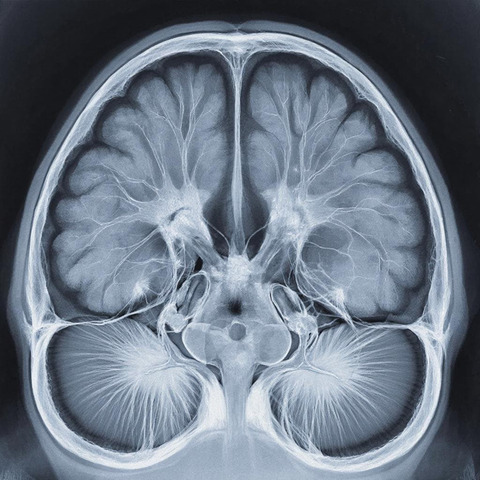

На Чукотке нейросети обучат расшифровывать КТ мозга

До конца 2026 года в больнице планируют подключить анализ компьютерной томографии головного мозга, а также запустить диагностику заболеваний по снимкам сетчатки глаза. Оба направления призваны повысить качество медицинской помощи в отдалённых районах, где доступ к узким специалистам ограничен. На эти цели из федерального и окружного бюджетов выделят порядка 8 млн рублей.